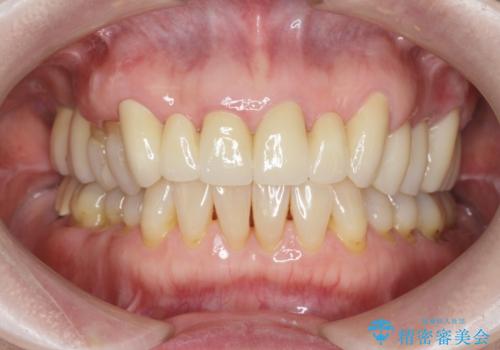

不自然な前歯ブリッジ ジルコニアブリッジによるやり替え

- 20年前に入れたブリッジの見た目の改善を求めて来院されました。

丁寧に現在装着されているブリッジを除去後、精度の高いジルコニアブリッジで審美性の改善を計画します。

- 66万円(仮歯・ジルコニアクラウン×6)費用は治療当時の料金となります

前歯に限らず拡大鏡を用いた精密な形成・シリコンを用いた精度の高い印象を徹底することで治療全体の質を高め、審美性だけでなく長期的な予後を期待することができます。